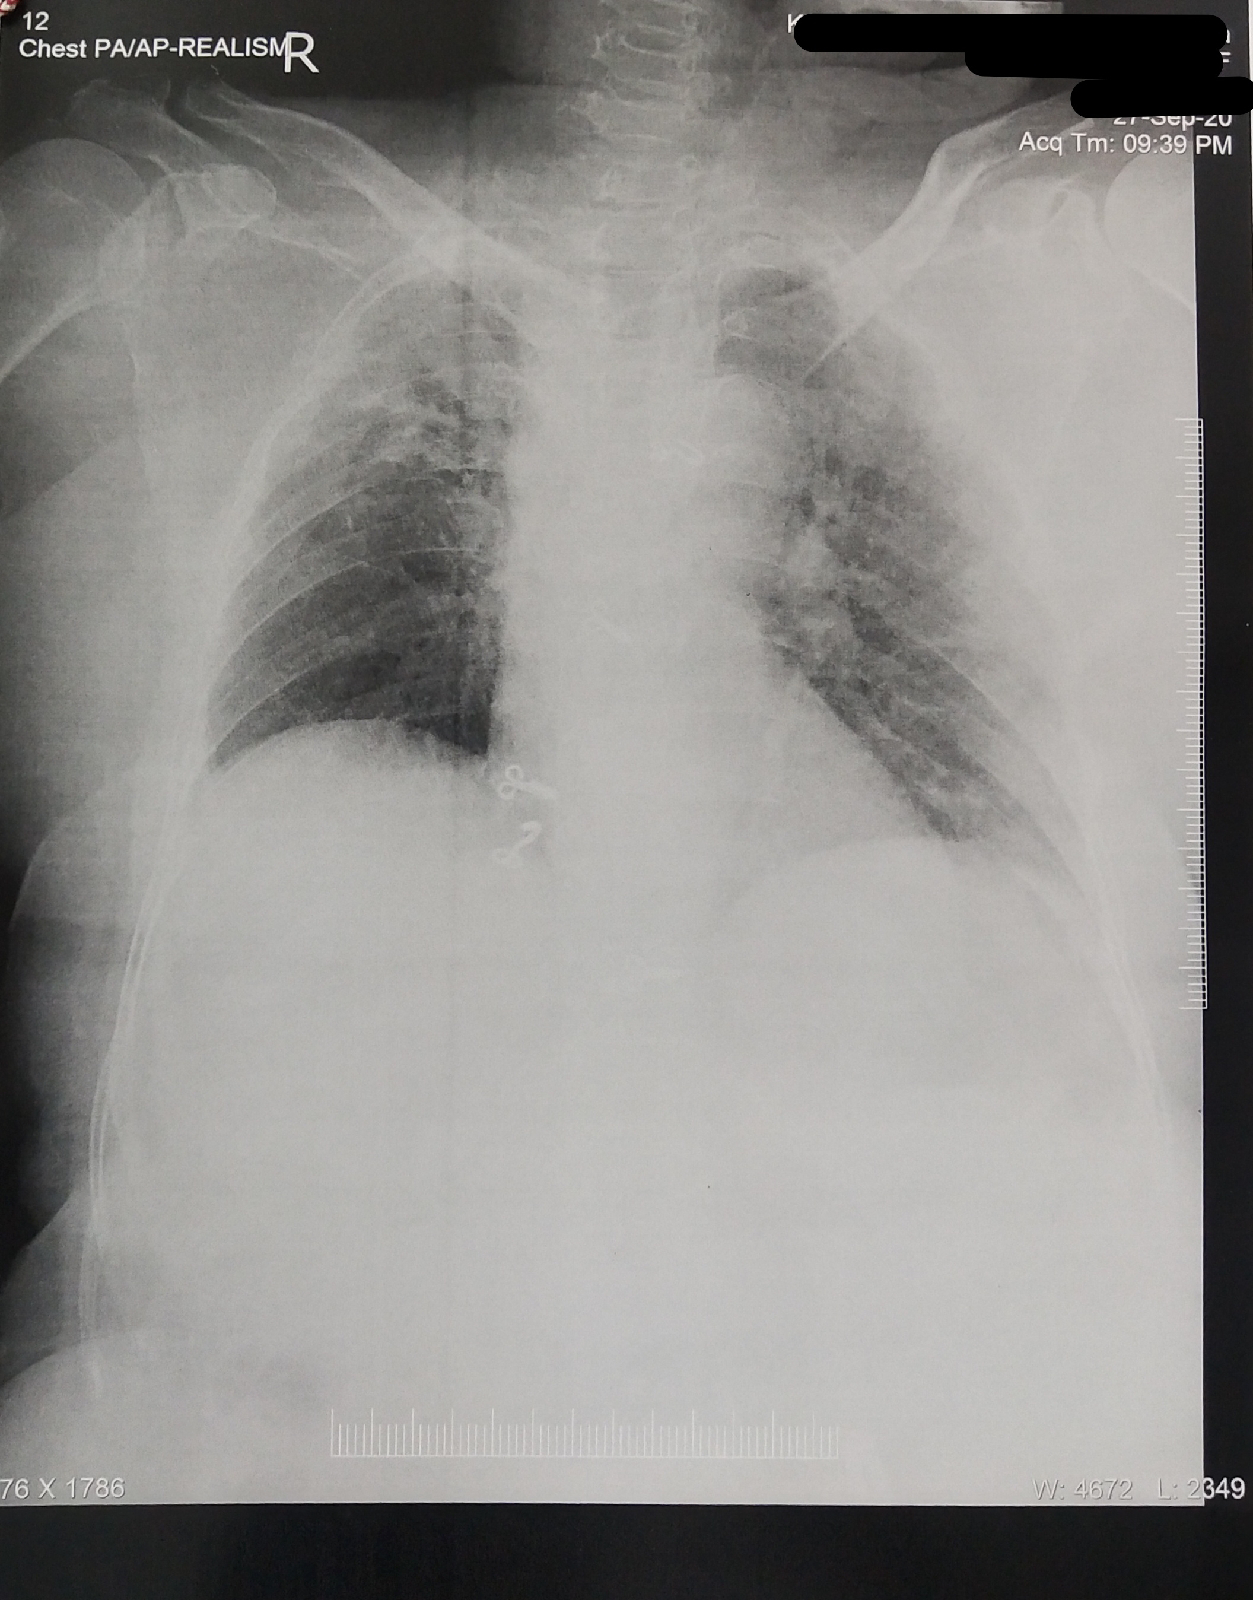

RS: BAE + crepitations are heard in right and left infra clavicular,right and left infra scapular regions

Patient may have right sidedcomplete hemiplegia with cardioembolic stroke due to MAT secondary to Rt ULL Fibrosis (?TB). De novo detected DM Type 2 and HTN with Diabetic Triopathy and Diabetic Dermopathy.

RS: BAE + crepts heard in right infraclavicular and B/L infra scapular areas